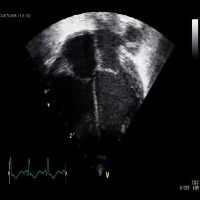

Medical Diagnostics: Medical professionals can employ the "echo_structures" model to improve patient care by facilitating the identification and analysis of cardiac structures via echocardiogram (ultrasound) images to provide a quicker and more accurate diagnosis of cardiovascular diseases and conditions.

Personal Health Monitoring: Integration of "echo_structures" model with mobile health apps and wearable devices (such as smartwatches) could allow for continuous and real-time monitoring of cardiac health, identifying abnormalities or potential concerns, and alerting users or healthcare providers when intervention may be needed.

Telemedicine Support: The "echo_structures" model could be incorporated into telemedicine platforms to assist remote medical professionals in diagnosing and treating cardiac conditions by allowing them to better understand patients' visual cardiac data and provide appropriate care from a distance.

Medical Research: Researchers in cardiology can utilize this model to efficiently process and analyze a large number of cardiac ultrasound images to study trends, monitor changes in heart structure or abnormalities, and support the development of novel medical approaches or innovative treatments for cardiovascular diseases.

Medical Training: The "echo_structures" model can serve as a valuable educational tool for medical students learning to read and interpret ultrasound images accurately. By automating the identification of cardiac structures, the model can provide immediate feedback, increasing students' learning efficiency and potentially improving overall diagnostic skills.